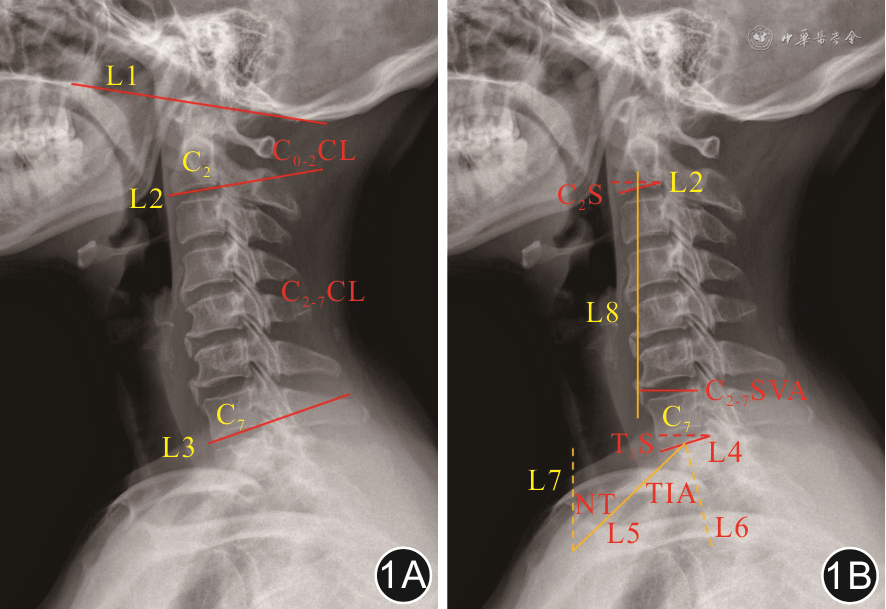

采用荷兰飞利浦Digital Diagnost 3 X线机摄片,侧位片患者取自然立位,目视前方并保持视线水平(颌眉角-10°~10°)。将颈椎侧位X线片由PACS(美国GE公司)导入Surgimap V2.3.2.1软件(美国Nemaris Inc公司)测量以下矢状面参数(图1)。

注:L1为McGregor线,即硬腭后缘和枕骨鳞部最低点的连线;L2为C2下终板切线;L3为C7下终板切线;L4为T1上终板切线;L5为胸骨柄近端上缘顶点与T1上终板中点连线;L6为T1上终板的中垂线;L7为通过胸骨柄上缘的垂线;L8为通过C2椎体中点的铅垂线;CL为颈椎前凸角;C2S为C2倾斜角;TIA为胸廓入口角;T1S为T1倾斜角;NT为颈倾角;C2~7 SVA为C2~7矢状轴距离

(1)C0~2及C2~7颈椎前凸角(cervical lordosis,CL):McGregor线(硬腭后缘至枕骨鳞部最低点的连线)与C2下终板切线间的夹角即C0~2 CL,C2下终板切线和C7下终板切线间的夹角即C2~7 CL;(2)C2倾斜角(C2 slope,C2S):C2下终板切线与水平线的夹角;(3)胸廓入口角(thoracic inlet angle,TIA):胸骨柄近端顶点与T1上终板中点间连线,该连线与T1上终板中垂线之间的夹角即TIA;(4)T1S:T1上终板切线与水平线间的夹角;(5)颈倾角(neck tilt,NT):胸骨柄近端上缘顶点与T1上终板中点间连线,该连线与通过胸骨柄上缘所做垂线之间的夹角即NT;(6)枕颈倾斜角(occipito-cervical inclination,OCI):McGregor线与C4椎体后缘切线间的夹角;(7)C2~7 SVA:通过C2椎体中点做铅垂线,C7椎体后上角与此铅垂线间的垂直距离。